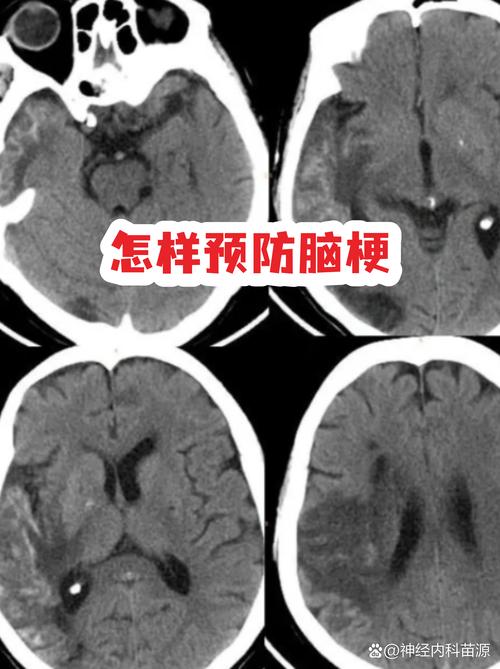

脑梗糖尿病的平均寿命

(图片来源网络,侵删)